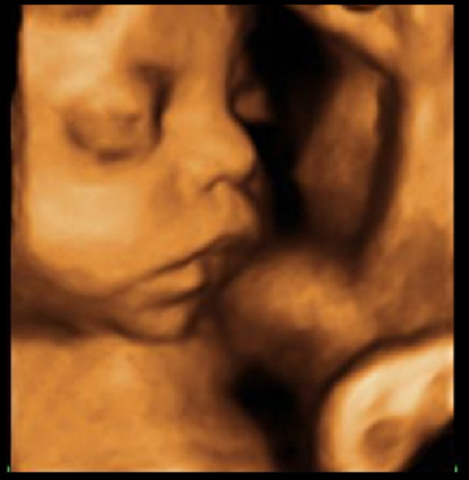

Empieza a desarrollarse el sentido del tacto: ya se han formado los receptores de la sensibilidad cutánea de los dedos. El aparato gustativo también empieza a funcionar y el feto se familiariza con el sabor del líquido amniótico en el que flota y que absorbe por la piel o tragándolo. La cabeza tiene un aspecto menos desproporcionado con respecto al resto del cuerpo. Las manos están completamente formadas.

• 16.a-18.a semanas

La piel ya no es tan fina, aunque sigue siendo transparente y deja ver los vasos sanguíneos. El cabello crece. Los músculos se fortalecen y los movimientos son más vigorosos: la madre empieza a sentirlos. Pero el esqueleto todavía no está osificado del todo. Para muchos padres, gracias a la eco grafía este 4.º mes es también el momento de una revelación: pueden ver a ese hijo. Al final de este 4.º mes, el feto mide casi 20 cm y pesa 250 g.